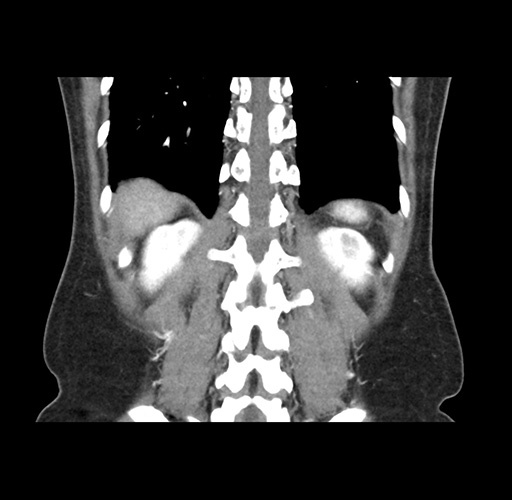

Imaging Analysis

Look through the patient's CT scan to identify any areas of concern for the necessary procedure.

Based on your CT findings, which issue(s) would give reason for "planned slowing down moment(s)" in this case?